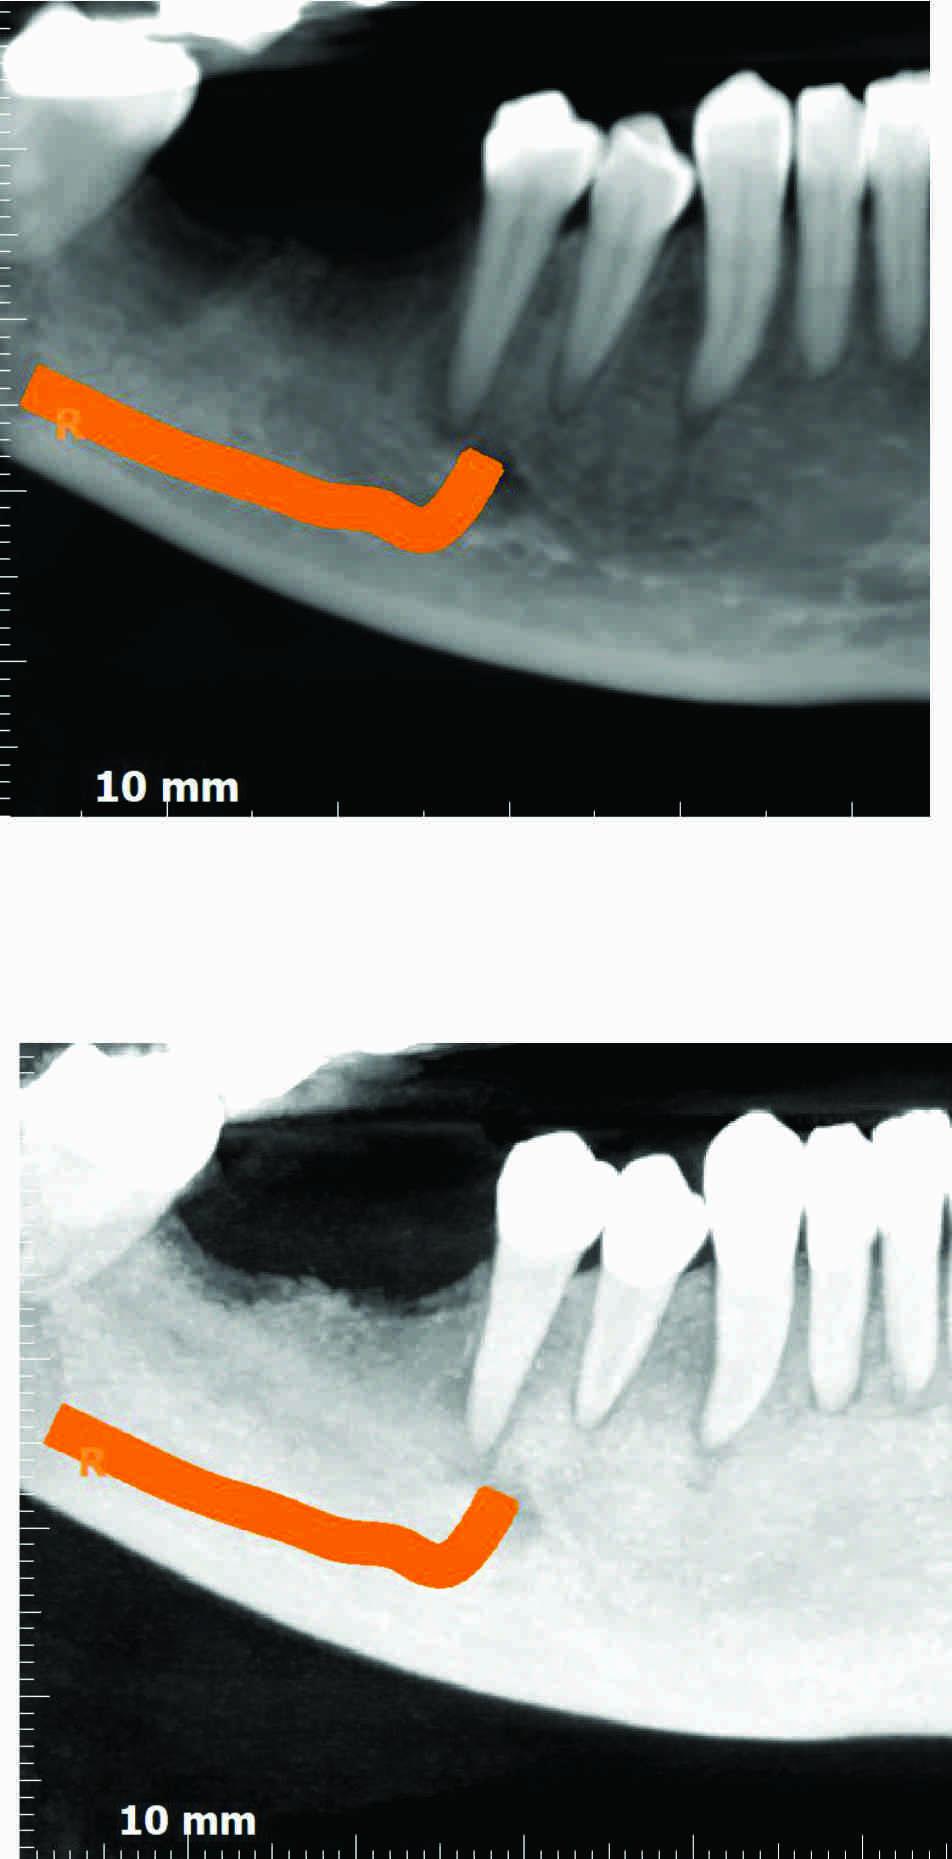

Lower right 1st and 2nd molar extracted around 6 months ago. A few images of the case are in the first reply to this post .

Distance between LR 2nd premolar and LR 3rd molar is 15 mm.